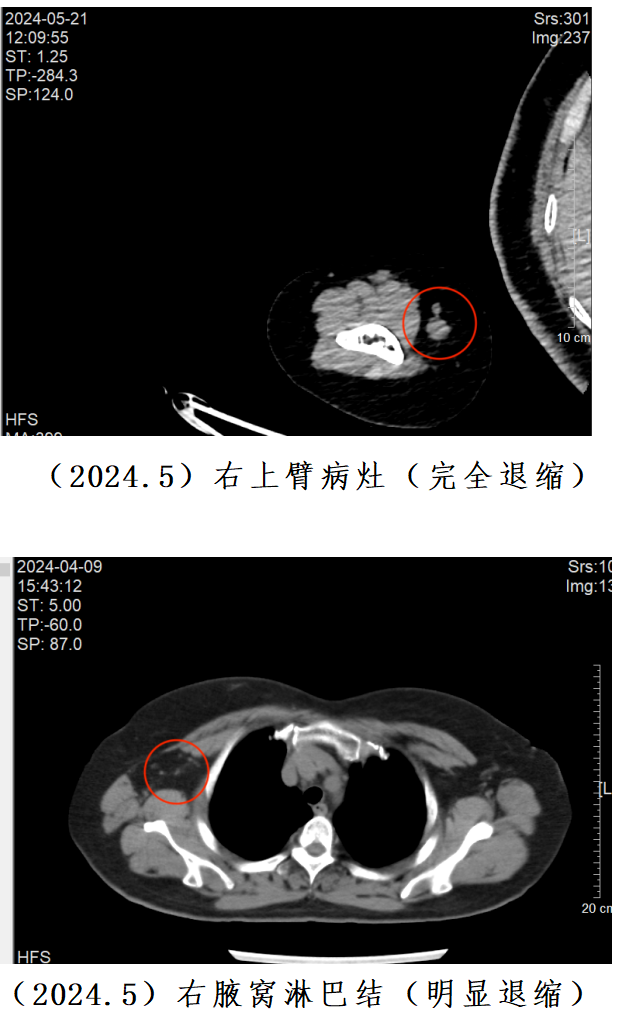

最初,郭女士对参与临床研究抱有疑虑,担心未知的治疗方案可能带来的风险和不确定性。但随着时间的推移和治疗的深入,她的态度发生了明显变化。在6周的治疗后,她的肿瘤就缩小了30.26%。一年多来,郭女士相继完成了22周期的“DNV3+特瑞普利单抗”治疗,肿瘤持续稳定退缩。最近一次复查,肿瘤相比最初缩小了58.56%,病情取得阶段性控制。